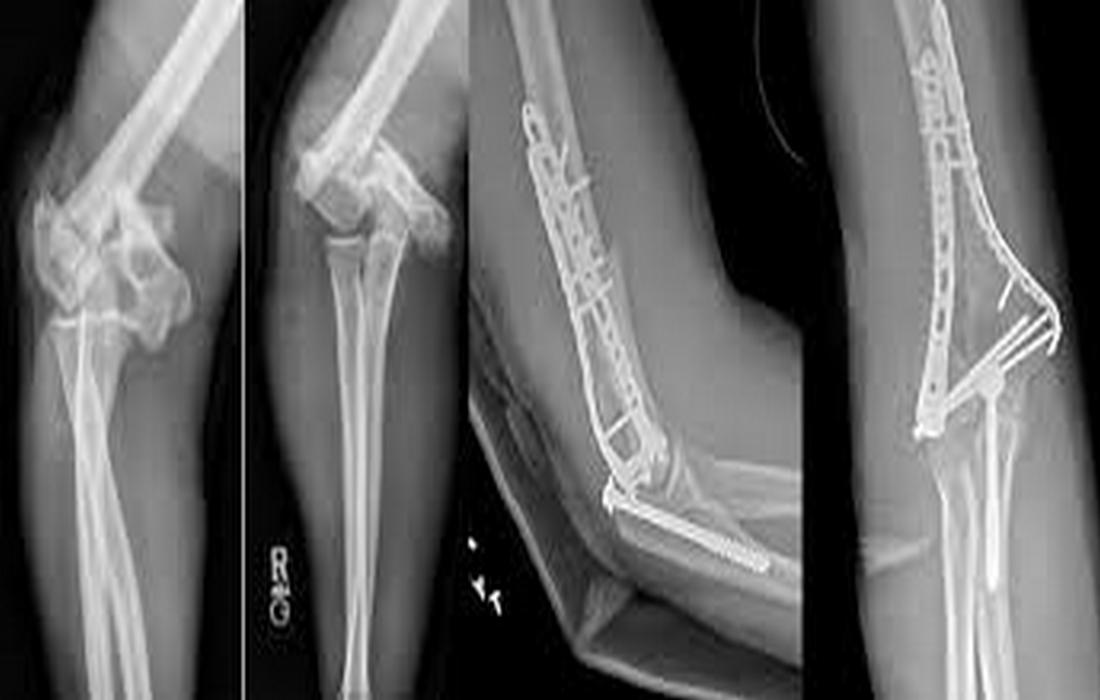

• Χειρουργική: τα περισσότερα κατάγματα ωλεκράνου χρειάζονται επέμβαση, με τεχνικές όπως σύρμα-τενόντια ραφή, πλάκες και βίδες, για την αποκατάσταση της ανατομίας και της κίνησης.

• Οστεοσύνθεση με βίδες και πλάκες: για σταθερή αποκατάσταση του κατάγματος.